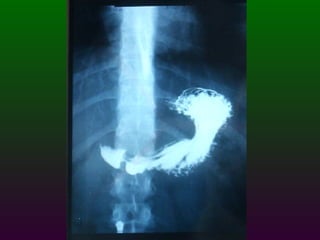

S.E.G.D.  Serie esófago gastro duodenal Definición  Estudio de doble contraste (bario) y aire del tracto digestivo superior. (esófago, estómago, duodeno)

SEGD ENFERMEDADES DEL ESTÓMAGO Y DUODENO DIVISIÓN ANATÓMICA DEL ESTÒMAGO CARDIAS  FONDO CUERPO  ANTRO  PÍLORO

SEGD ENFERMEDADES DEL ESTOMAGO Y DUODENO El duodeno se divide en cuatro porciones; que se extienden desde el píloro hasta el ligamento de Treitz. La primera porción se denomina bulbo duodenal.